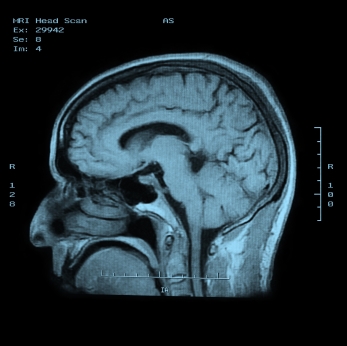

Заболевание нервной системы, проявляющееся длительной, мучительной головной болью при отсутствии морфологических повреждений головного мозга, опухолей, повышения давления. В основе лежат нарушения регуляции сосудистого тонуса, сужение либо неравномерное расширение сосудов головного мозга. Как правило, приступы длятся от 4 до 72 часов.

ДИАГНОСТИКА

Изучение истории болезни и медицинский осмотр не проводятся. Тесты, чтобы исключить другие причины головных болей может быть сделано.